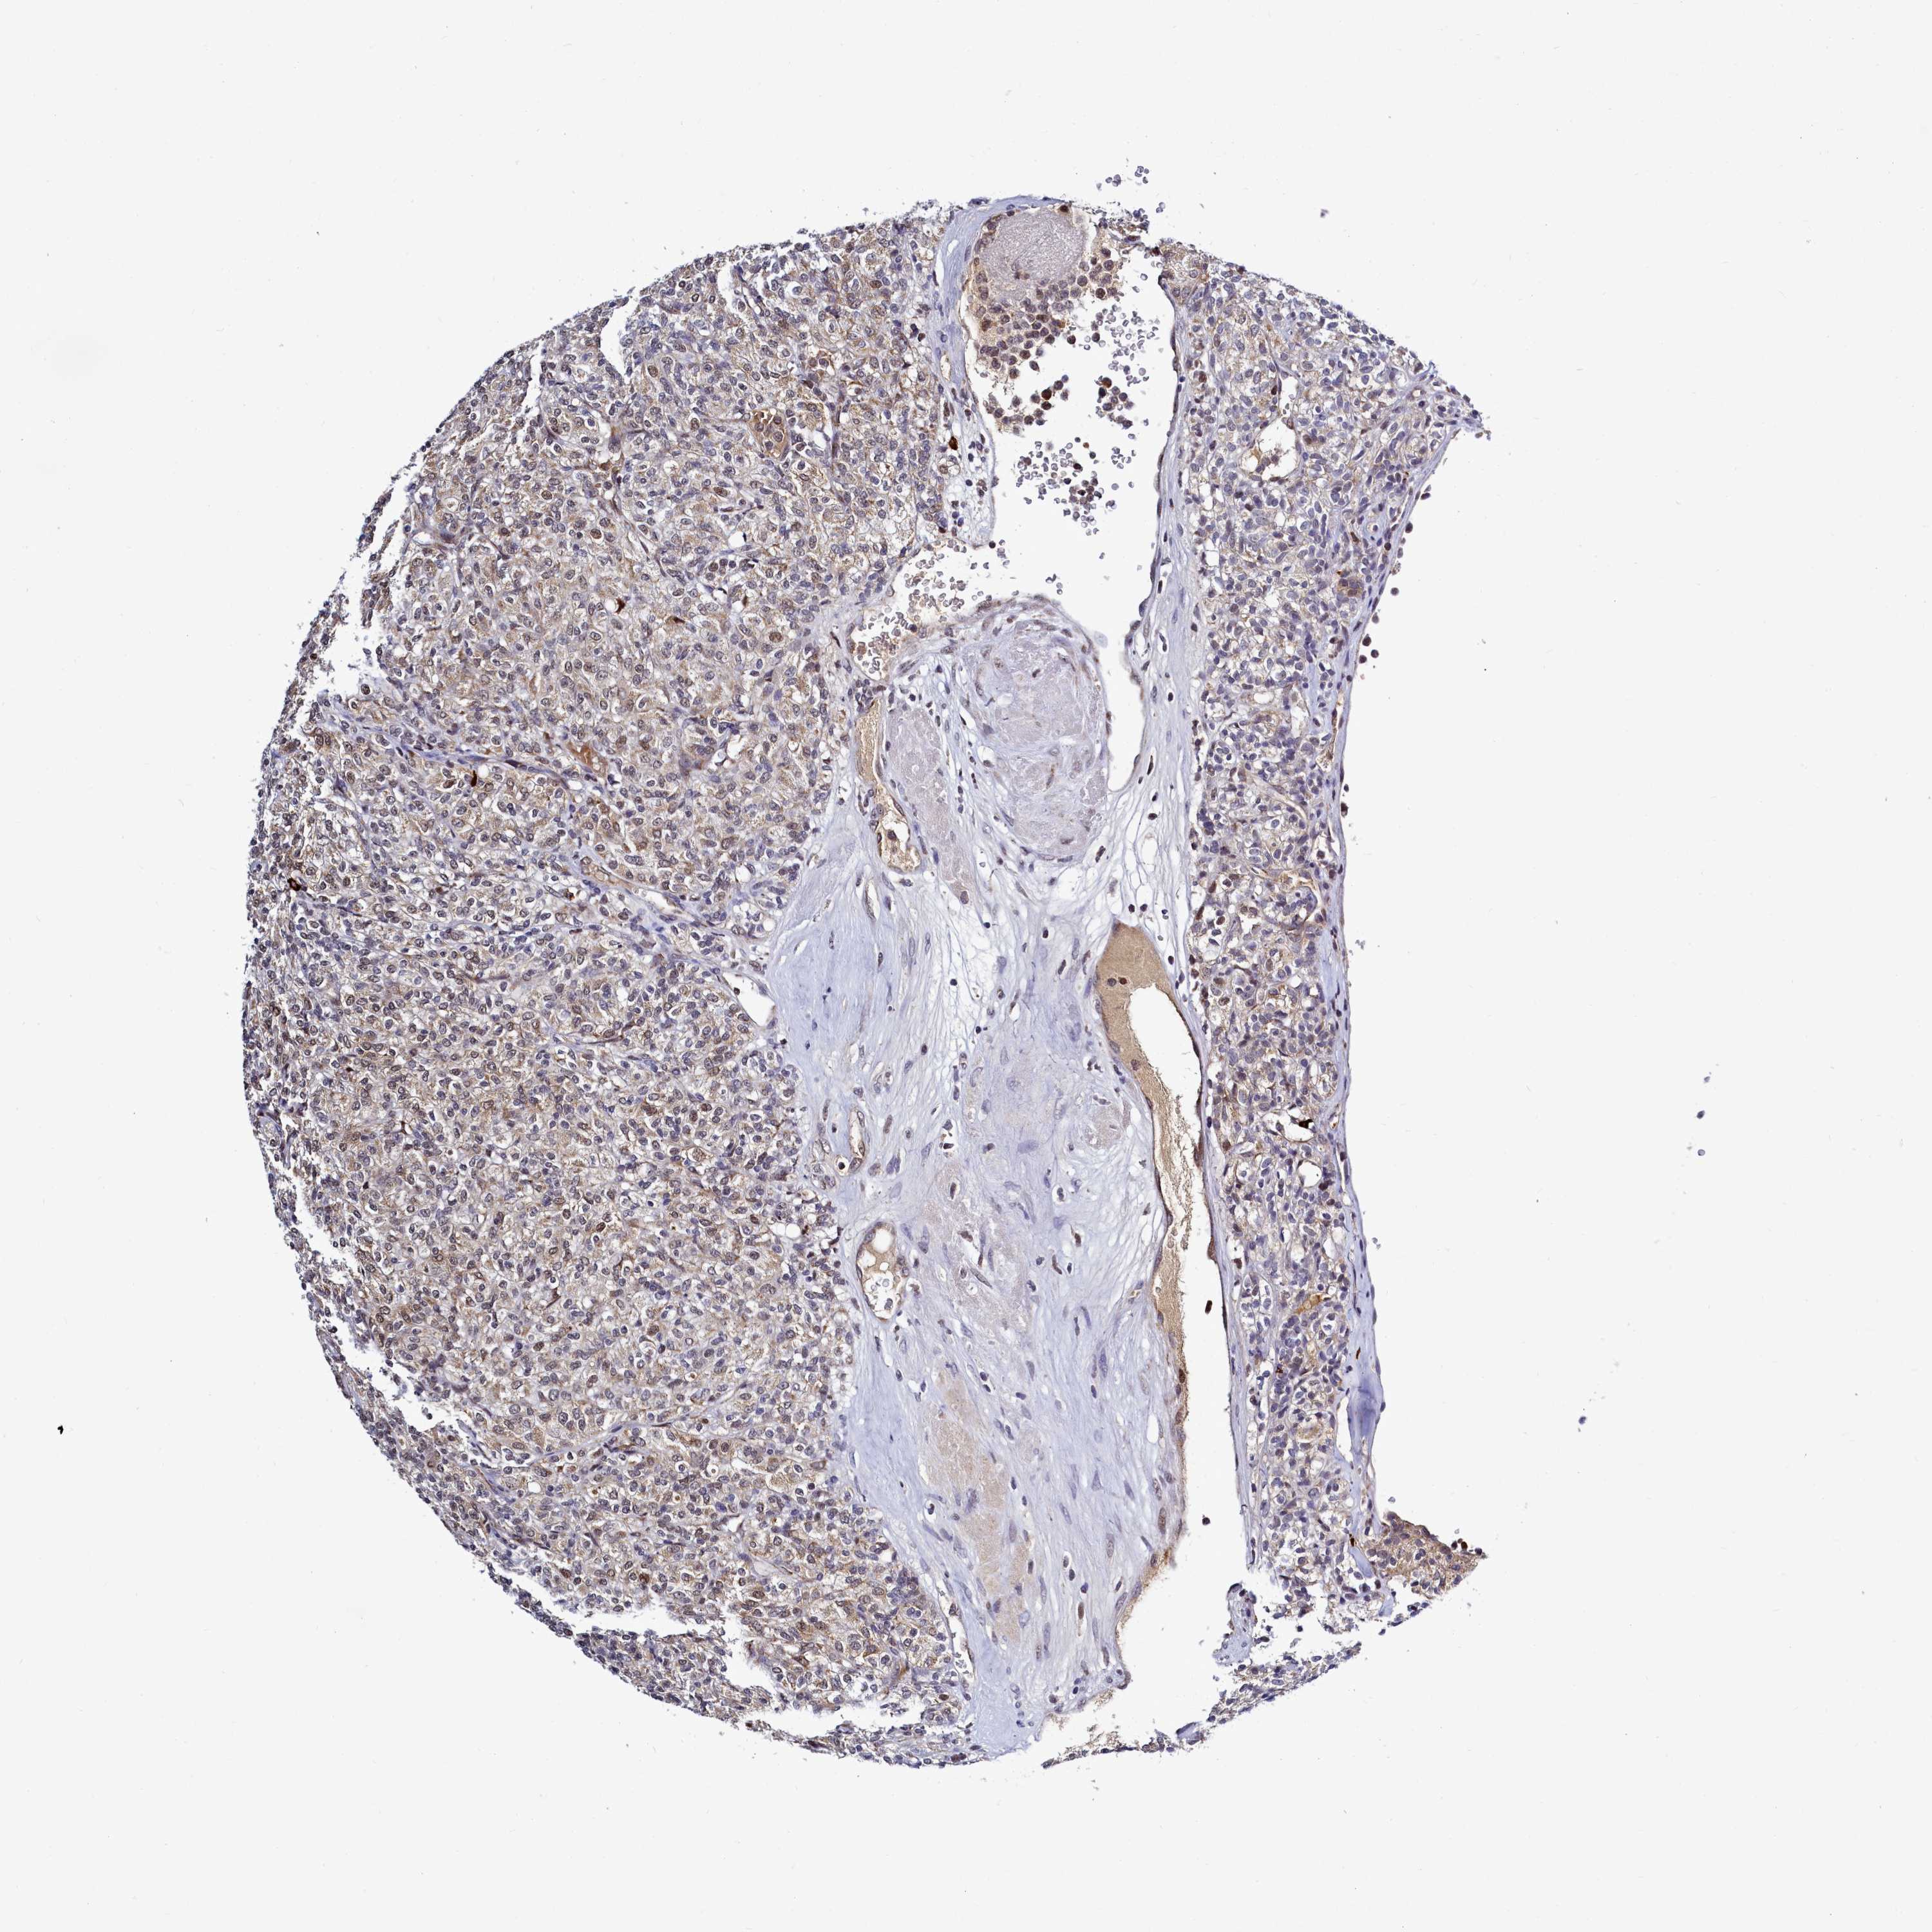

KIDNEY RENAL CLEAR CELL CARCINOMA (VALIDATION) - Interactive survival scatter ploti

The Survival Scatter plot shows the clinical status (i.e. dead or alive) for all individuals in the patient cohort, based on the same data that underlies the corresponding Kaplan-Meier plots. Patients that are alive at last time for follow-up are shown in blue and patients who have died during the study are shown in red.

The x-axis shows the expression levels (FPKM) of the investigated gene in the tumor tissue at the time of diagnosis. The y-axis shows the follow-up time after diagnosis (years). Both axes are complimented with kernel density curves demonstrating the data density over the axes. The top density plot shows the expression levels (FPKM) distribution among dead (red) and alive patients (blue). The right density plot shows the data density of the survived years of dead patients with high and low expression levels respectively, stratified using the cutoff indicated by the vertical dashed line through the Survival Scatter plot. This cutoff is automatically defined based on the FPKM cutoff that minimizes the p-score. The cutoff can be changed by dragging the vertical line or by entering a cutoff value in the square labeled "Current cut-off".

Under the Survival Scatter plot the p-score landscape (black curve; left axis) is shown together with dead median separation (red curve; right axis). Dead median separation is the difference in median mRNA expression between patients who have died with high and low expression, respectively. It is calculated as follows: median FPKM expression of dead patients with high expression - median FPKM expression of dead patients with low expression. This is intended to aid the user in visually exploring custom cutoffs and the associated p-scores and dead median separation.

Individual patient data is displayed and can be filtered by clicking on one or more of the category buttons on the top of the page. Categories describing expression level and patient information include: high, low, alive, dead, female, male and tumor stages. The scale of the x-axis can be toggled between linear and log-scale by clicking on the "x log" button. Mouse-over function shows TCGA ID, patient information and mRNA expression (FPKM) for each patient.

& Survival analysisi

Kaplan-Meier plots summarize results from analysis of correlation between mRNA expression level and patient survival. Patients were divided based on level of expression into one of the two groups "low" (under cut off) or "high" (over cut off). X-axis shows time for survival (years) and y-axis shows the probability of survival, where 1.0 corresponds to 100 percent.

POM121L2 is not prognostic in Kidney Renal Clear Cell Carcinoma (validation)

TCGA RNA samplesi

RNA-seq data is reported as average FPKM (number Fragments Per Kilobase of exon per Million reads), generated by the The Cancer Genome Atlas (TCGA) .

Normal distribution across the dataset is visualized with box plots, shown as median and 25th and 75th percentiles. Points are displayed as outliers if they are above or below 1.5 times the interquartile range. FPKM values of the individual samples are presented next to the box plot.

Average pTPM 0.0

Number of samples 100